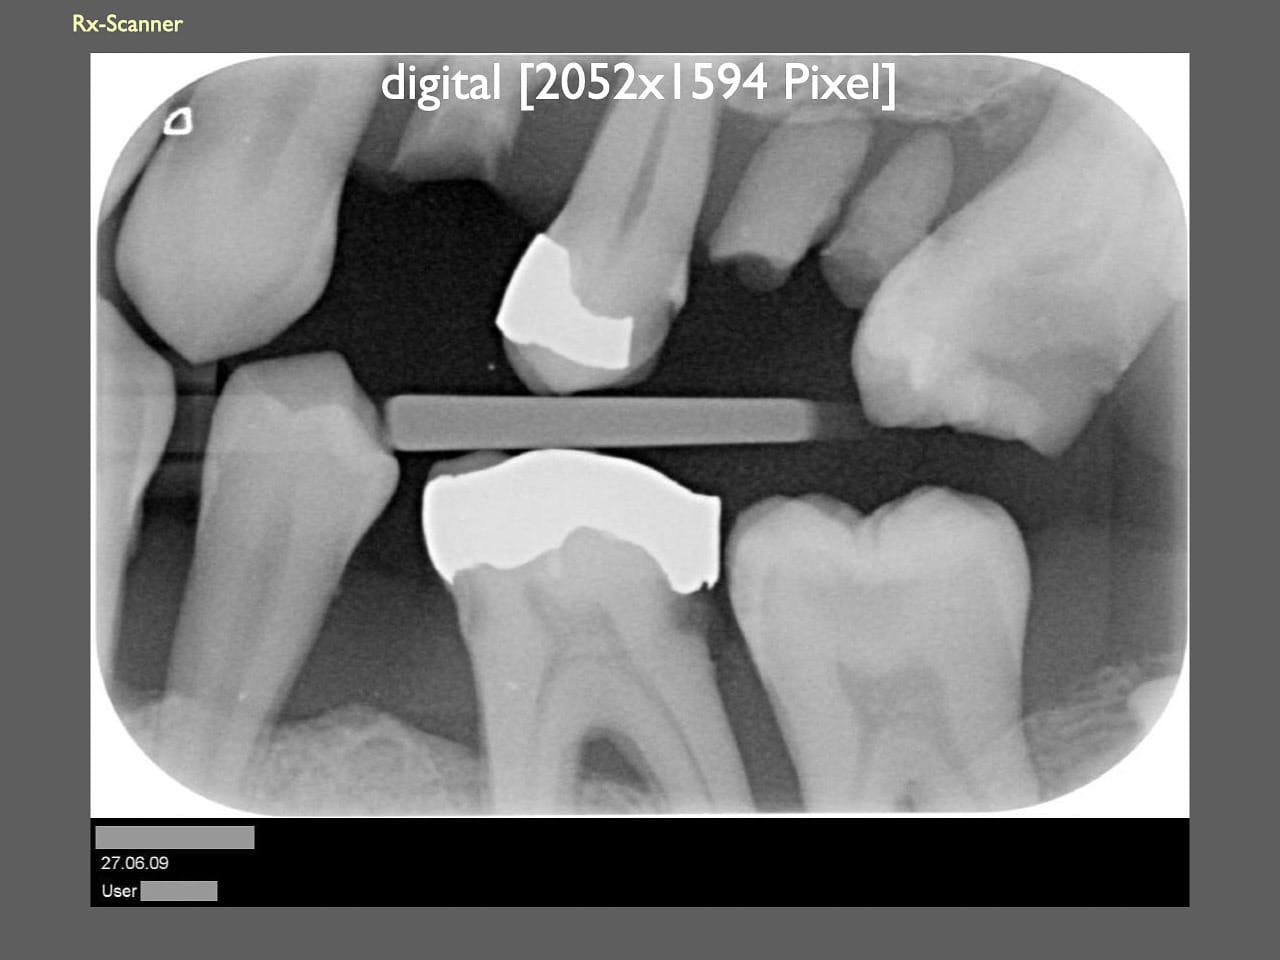

dental Scannen in der Zahnarztpraxis. Study Club vom 28.2.2010. Von peter portmann, Veröffentlicht am 28. Feb. 2010 — 3 min Lesezeit dokumentationfoto Auf dieser Seite Zahnarztpraxis-Trilogie zu Fotografie und Dokumentation Portrait Fotografie Scannen Scannen